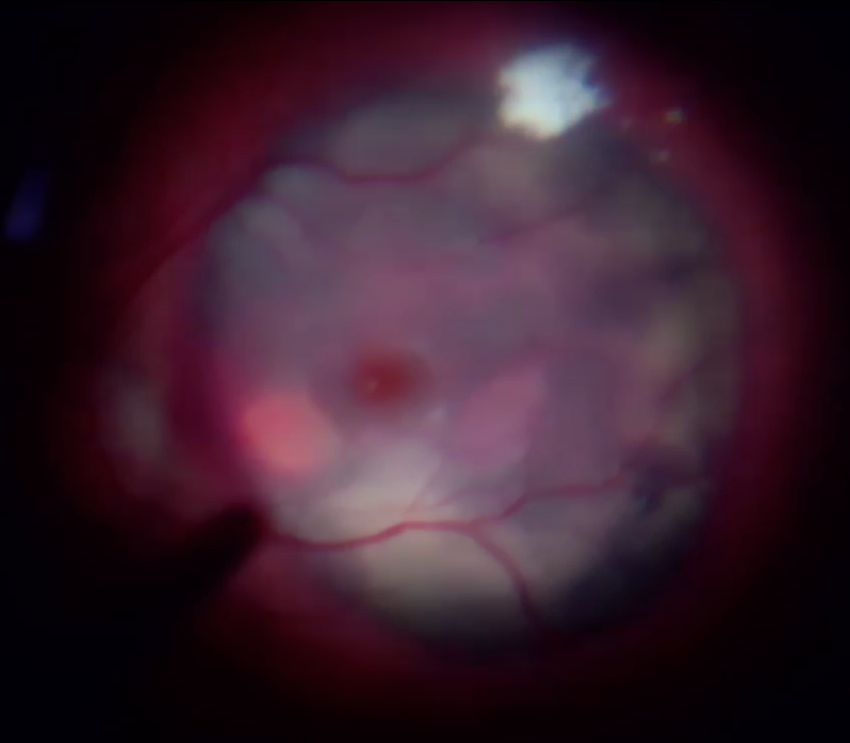

Об'єктивно - на правому оці субретинальний крововилив від аркади до аркади, з елементами субпігментного крововиливу, кров у стадії розсмоктування й у деяких ділянках фіброзування згустку.

В операційній перше, що привернуло увагу - це щільна адгезія скловидного тіла до сітківки, але це питання було вирішено вітреотомом та кеналогом.

Після діатермії було виконано дренуючу ретинотомію на межі крововиливу (можна було би ще ближче до центру, але не хотілося потім виконувати лезеркоагуляцію поблизу до СНМ) та частково роздреновано субретинальній простір.

В подальшому з використанням пухиря ПФОС на сітківці та пухиря стерильного повітря під сітківкою виконано розрідження та дислокація субретинального крововиливу з аспірацією рідкого гему крізь дренуючу ретинотомію.